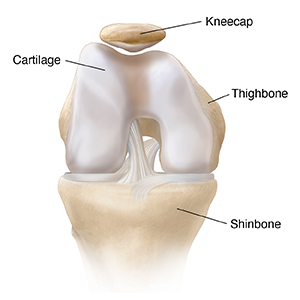

A closer view of the kneecap shows the difference between the smooth cartilage and the rougher bone beneath.

From the back, you can see cartilage. This is tough, cushiony tissue that covers the bone. It helps the kneecap slide easily against the thighbone.

From the top, you can see that the kneecap sits in a groove or “track” in the thighbone.